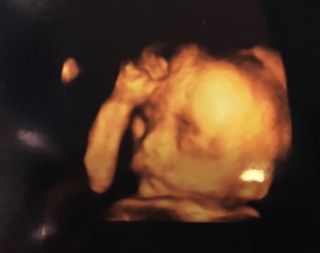

写真:23w2d:ジジさん

4人目にして初めての 4Dエコー‼︎

技師さん頑張ってくれて可愛いお顔が見えました♡

頭の大きさ5.5cm✩.*˚ 全体的に3~4日分程小さめとの事でした(*ˊᵕˋ*) 目が大きくて鼻が小さくてとっても可愛いかった( ´,,•ω•,,`)♡ 早く会いたいよ〜楽しみだなっ✩°。⋆⸜(*˙꒳˙* )⸝